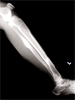

Segmental Tibia Fracture

By: Dr Sarbjit Singh

Pre

Op

52year old Thai female with closed segmental fracture tibia following a road traffic accident